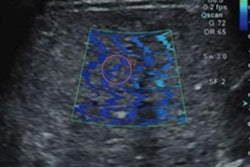

Jae Seok Bae, MD, from Seoul National University Hospital presented research at RSNA showing the efficacy of shear-wave elastography in predicting chemotherapy response in colorectal patients.Amerigo Allegretto

Shear-wave elastography measures changes in tumor stiffness between and after chemotherapy to predict pathological response in patients. Previous studies have shown its efficacy in this area for breast cancer.

Bae and colleagues sought to study the prognostic role of shear-wave velocity value for predicting chemotherapeutic response and progression-free survival in colorectal cancer patients. In its prospective single-center study, the team used shear-wave elastography on metastases before and after the start of chemotherapy.